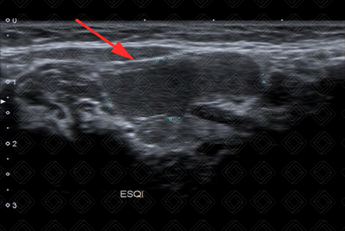

Texto alternativo para a imagem Figura 2. Créditos: Dra. Elazir Mota - Rio de Janeiro/RJ

Descrição das figuras 1 e 2: Ultrassonografia cervical evidenciando lesão cística, predominantemente hipoecoica, no espaço sublingual esquerdo, herniando através de uma falha no músculo milo-hiodeo (setas vermelhas), compatível com rânula simples.

• Ultrassonografia cervical: Imagem anecoica/hipoecoica, de paredes finas, bem definida, acima do músculo milo-hioide, no assoalho da boca. A lesão pode apresentar grumos de debris no seu interior e aumento da ecogenicidade do tecido subcutâneo adjacente, quando infectado (figura 1);